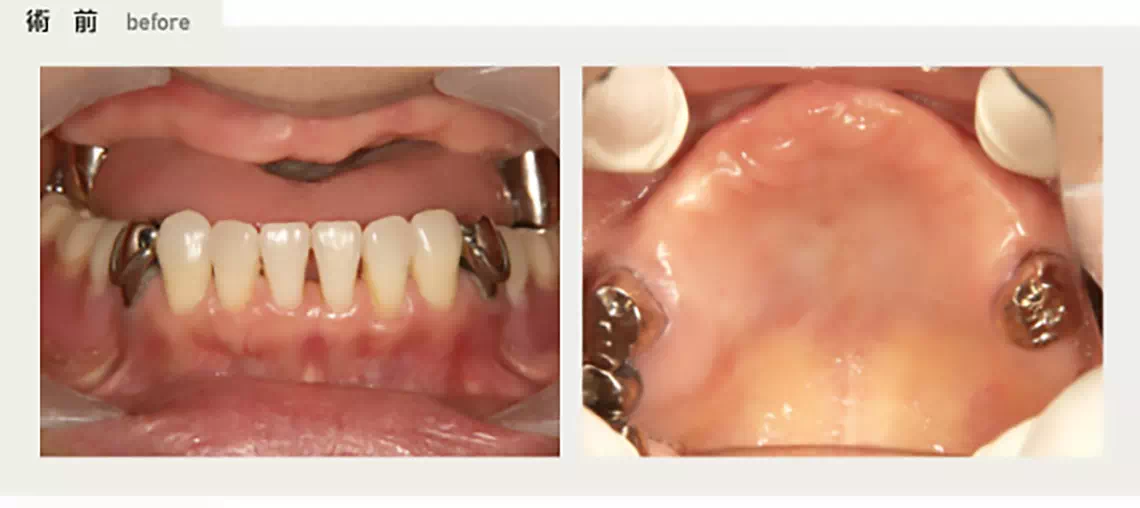

ほとんど歯の無い方 50代 女性

30代より徐々に歯がなくなり入れ歯にしていましたが、発音によっては入れ歯がはずれてしまい困っていました。インプラントで外れない綺麗な歯が欲しいという要望で、上顎にインプラント治療を行うことになりました。